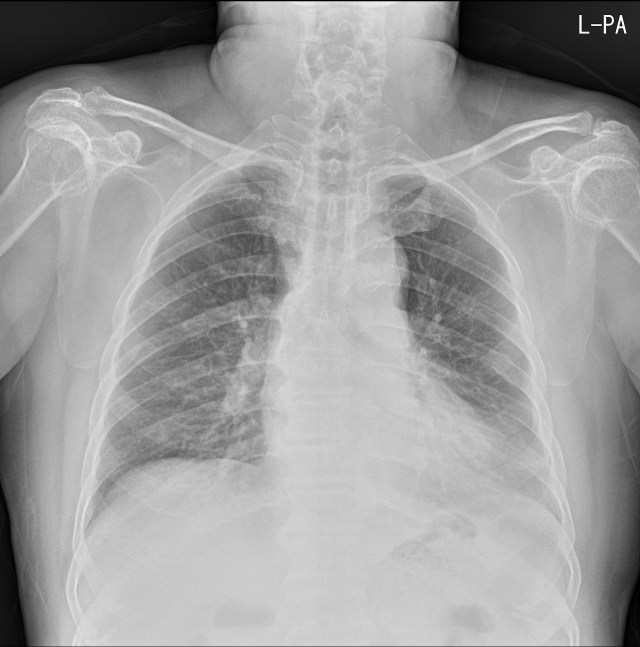

65세 남자환자로 기침과 가래 및 청진상 호홉잡음이 들려 촬영한 단순흉부X선영상입니다. 좌측심장경계가 분명하지 않은 반면, 횡격막윤곽은 비교적 뚜렷하게 보여서 좌측폐 설상엽에 병변 가능성이 의심됩니다.